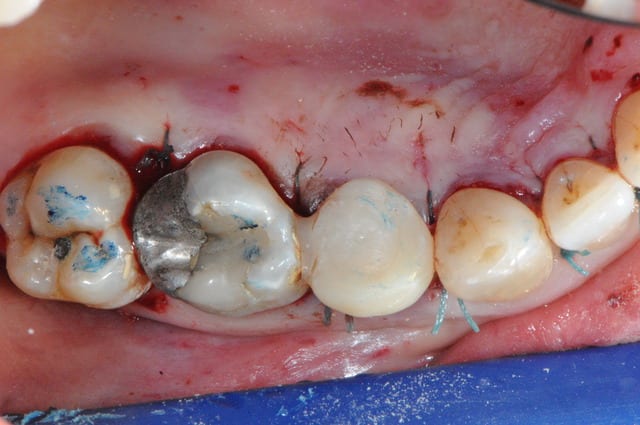

voici un cas avec extraction de 2iéme prémolaire incluse par voie palatine (25) et extraction - implantation - mise en charge immédiate sur 24.

bon , fin du suspense.

1 aspect extérieure

2-3-4-5 décollement

6 l’objet du délit...